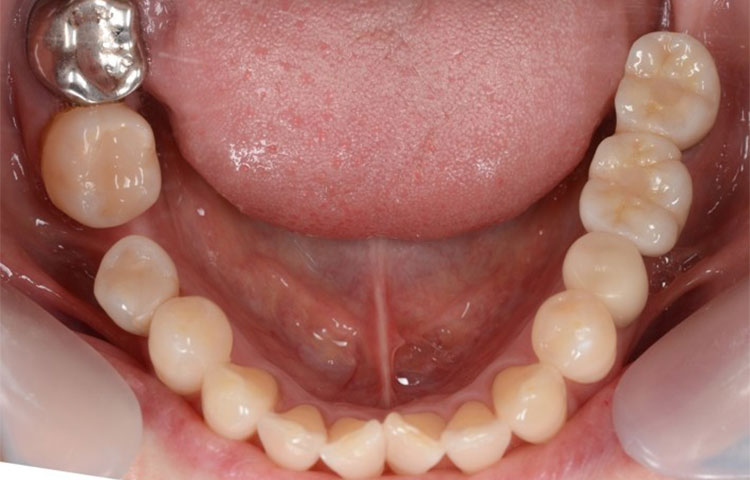

インプラント症例 Case2

Treatment cases

Before

After